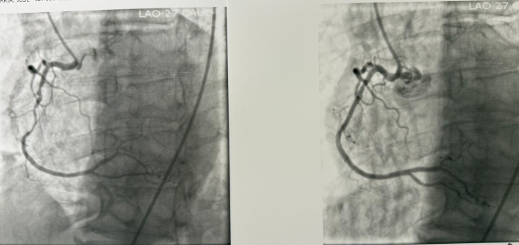

Stent placement after balloon angioplasty widens a narrowed coronary artery.

- During the procedure, a small balloon attached to a thin catheter is guided to the site of the blockage. The balloon is gently inflated to widen the artery and restore blood flow. In most cases, a small flexible wire mesh tube called a stent is placed inside the artery to help keep it open permanently.

- PCI improves blood flow to the heart muscle, relieves chest pain (angina), and may reduce heart damage during or after a heart attack. It is often performed immediately following a diagnostic cardiac catheterization when a significant blockage is found.